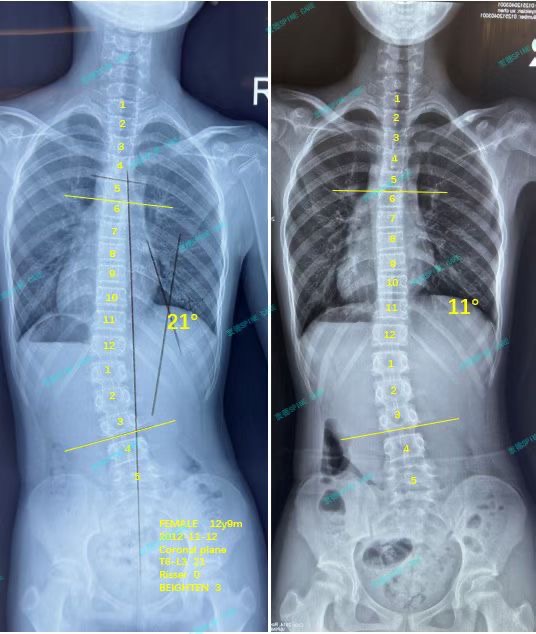

我是Carol,三个月从21度到11度,感谢杨博士的专业!

案例主人:Carol 发现侧弯年龄:13岁 侧弯情况:Cobb角度21度

就这样坚持了三个月后,x片显示我的腰弯从21度降到了11度,我们都非常高兴!不用全天都戴着难受的支具,只要我坚持下来每天的训练,就会有很好的收获!

After persisting in this way for three months, x-ray showed that my waist bend dropped from 21 degrees to 11 degrees. We were all very happy! I don't have to wear uncomfortable braces all day long. As long as I persist in training every day, I will have good gains!